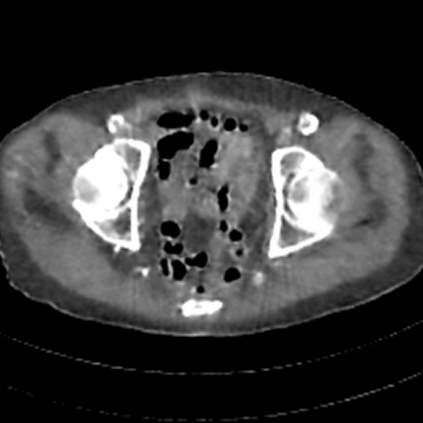

Sparse-view computed tomography (CT) -- using a small number of projections for tomographic reconstruction -- enables much lower radiation dose to patients and accelerated data acquisition. The reconstructed images, however, suffer from strong artifacts, greatly limiting their diagnostic value. Current trends for sparse-view CT turn to the raw data for better information recovery. The resultant dual-domain methods, nonetheless, suffer from secondary artifacts, especially in ultra-sparse view scenarios, and their generalization to other scanners/protocols is greatly limited. A crucial question arises: have the image post-processing methods reached the limit? Our answer is not yet. In this paper, we stick to image post-processing methods due to great flexibility and propose global representation (GloRe) distillation framework for sparse-view CT, termed GloReDi. First, we propose to learn GloRe with Fourier convolution, so each element in GloRe has an image-wide receptive field. Second, unlike methods that only use the full-view images for supervision, we propose to distill GloRe from intermediate-view reconstructed images that are readily available but not explored in previous literature. The success of GloRe distillation is attributed to two key components: representation directional distillation to align the GloRe directions, and band-pass-specific contrastive distillation to gain clinically important details. Extensive experiments demonstrate the superiority of the proposed GloReDi over the state-of-the-art methods, including dual-domain ones. The source code is available at https://github.com/longzilicart/GloReDi.